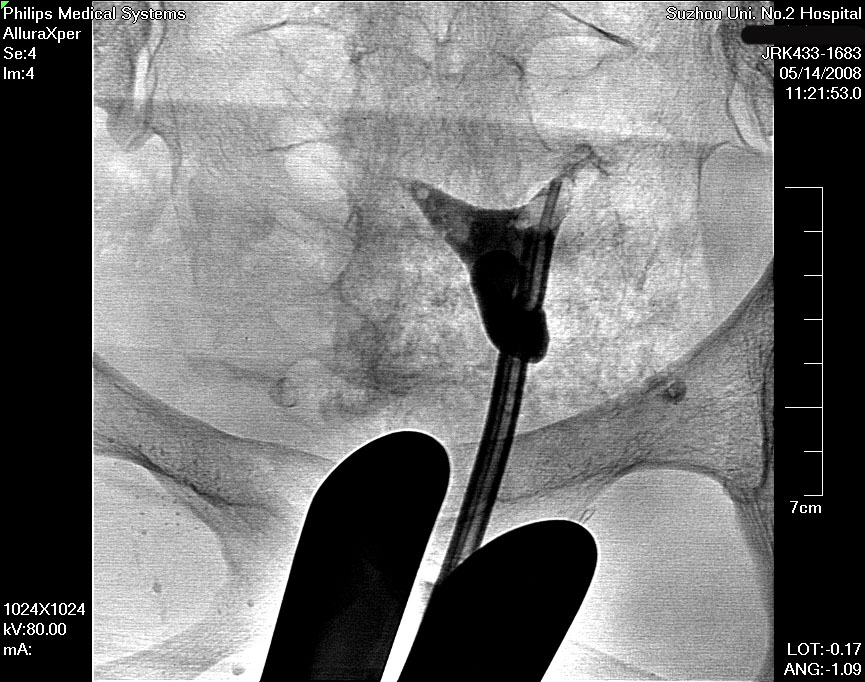

在清晰的DSA(数字减影血管造影机)的同步监测,采用同轴导管系统,进行输卵管选择性造影和再通术,主要适用于输卵管阻塞于间质部及狭部的不孕症患者,各段输卵管阻塞均可行选择性输卵管造影、通液。主要采用导管扩张术,插入导管导丝,利用导管导丝的推进扩张分离作用和造影剂的冲击力等,使输卵管疏通至伞端。手术安全高效,痛苦小,无需住院,复通率及术后妊娠率均较高。(见图1术前HSG宫腔形态正常,双侧输卵管不显影、图2左侧输卵管顺利通过导丝后造影剂通过畅、图3右侧输卵管通过导丝后畅)